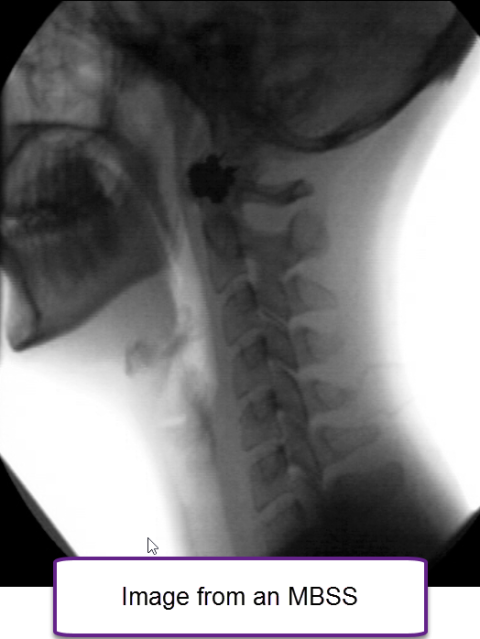

Our expert team utilizes imaging techniques—such as the Modified Barium Swallow Study (MBSS)—to assess swallowing function and detect abnormalities that may affect the esophagus. These diagnostic tools help us deliver precise, personalized care, ensuring each patient receives the most effective treatment for their condition.

Modified barium swallow study (MBSS)

The MBSS is a fluoroscopic radiologic test performed to evaluate swallowing. It gives information on how efficiently an individual can move liquid or food from the mouth to the throat and then into the esophagus. This exam reveals if liquid or food is being aspirated (aspiration = material that goes down the wrong way, or specifically, enters the windpipe or trachea). A speech pathologist is the professional typically performing the test. The patient sits in a chair and swallows food and liquid. Everything swallowed has barium added to it. Barium material is used because it shows up on x-rays. The swallow study is recorded and the speech pathologist analyzes the study to determine if swallow structures are moving in an abnormal manner, if there is excess residue or aspiration (and why), and correlates the patient’s swallowing complaint to the observed swallowing behavior. The speech pathologist may ask the patient to perform behavioral maneuvers during the study, to try to improve swallow function. The speech pathologist may recommend swallow therapy. The speech pathologist will send a report based on study results to the referring physician.